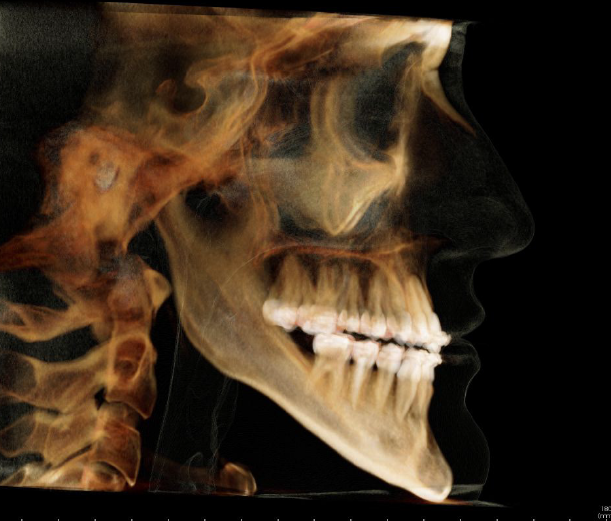

Vorher

Diagnose:

Maxilläre Retrognathie, OK-Schmalkiefer, Hyperdivergenz, erschwerter Lippenschluss